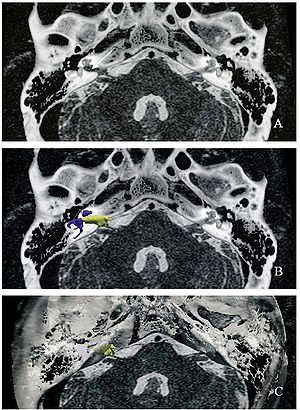

Publication: J Neurosurg. 2016 Jan 1:1-8. PMID: 26722859 Authors: Song F, Hou Y, Sun G, Chen X, Xu B, Huang JH, Zhang J. Institution: Department of Neurosurgery, People's Liberation Army General Hospital, Beijing, China. Background/Purpose: OBJECTIVE Preoperative determination of the facial nerve (FN) course is essential to preserving its function. Neither regular preoperative imaging examination nor intraoperative electrophysiological monitoring is able to determine the exact position of the FN. The diffusion tensor imaging-based fiber tracking (DTI-FT) technique has been widely used for the preoperative noninvasive visualization of the neural fasciculus in the white matter of brain. However, further studies are required to establish its role in the preoperative visualization of the FN in acoustic neuroma surgery. The object of this study is to evaluate the feasibility of using DTI-FT to visualize the FN. Methods Data from 15 patients with acoustic neuromas were collected using 3-T MRI. The visualized FN course and its position relative to the tumors were determined using DTI-FT with 3D Slicer software. The preoperative visualization results of FN tracking were verified using microscopic observation and electrophysiological monitoring during microsurgery. Results Preoperative visualization of the FN using DTI-FT was observed in 93.3% of the patients. However, in 92.9% of the patients, the FN visualization results were consistent with the actual surgery. CONCLUSIONS DTI-FT, in combination with intraoperative FN electrophysiological monitoring, demonstrated improved FN preservation in patients with acoustic neuroma. FN visualization mainly included the facial-vestibular nerve complex of the FN and vestibular nerve. |